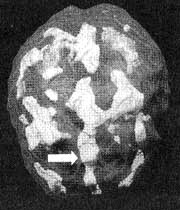

Мозг Роба. Результаты сканирования SPECT

Трехмерное изображение — активный мозг, вид сверху.

До лечения: обратите внимание на выраженное усиление активности в поясной системе (см. стрелку).

После лечение Anafranil. Активность поясной системы нормализовалась.

Трехмерное изображение — активный мозг, вид сбоку.

После трех лет неуклонного улучшения состояния на фоне приема Anafranil (оба раза, когда предпринимались попытки снизить дозу, симптомы возвращались), повторное сканирование показало нормализацию функции мозга.